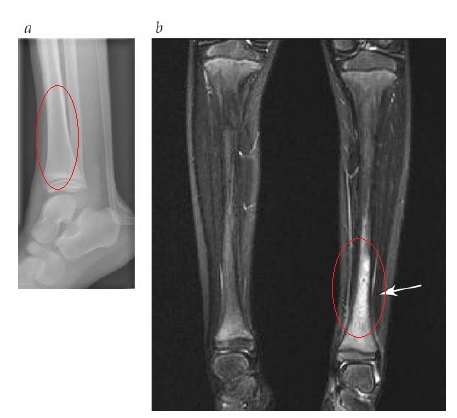

Esquerda RX / Direita RNM